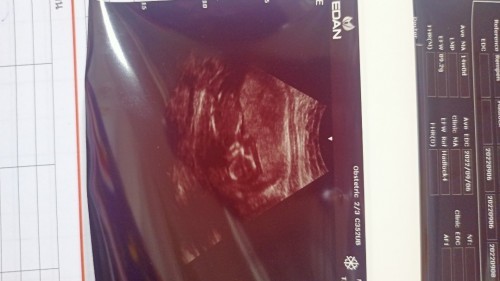

เป็นไปได้ไหมค่ะที่น้ำหนักลูกในท้องจะลดลงอาทิตย์ที่แล้วซาวที่คลีนิก33วีคซาวดูลูกน้ำหนัก2110กรัม อาทิตย์นี้34วีคซาวที่โรงบาลหมอบอกลูกเราหนัก1520กรัม หมอที่ซาวให้เป็นหมอฝึกหัดแต่หมอที่คลีนิกเป็นหมอใหญ่ผ่าตัด สรุปเราควรเชื่อใครดี แต่ใจเราเชื่อหมอคลีนิกมากกว่าหมอที่โรงบาลค่ะ #ขอคำแนะนำหน่อยค่ะ #ท้องแรกคะ #ขอบคุณล่วงหน้านะคะ #ขอบคุณสำหรับคำตอบค่ะ